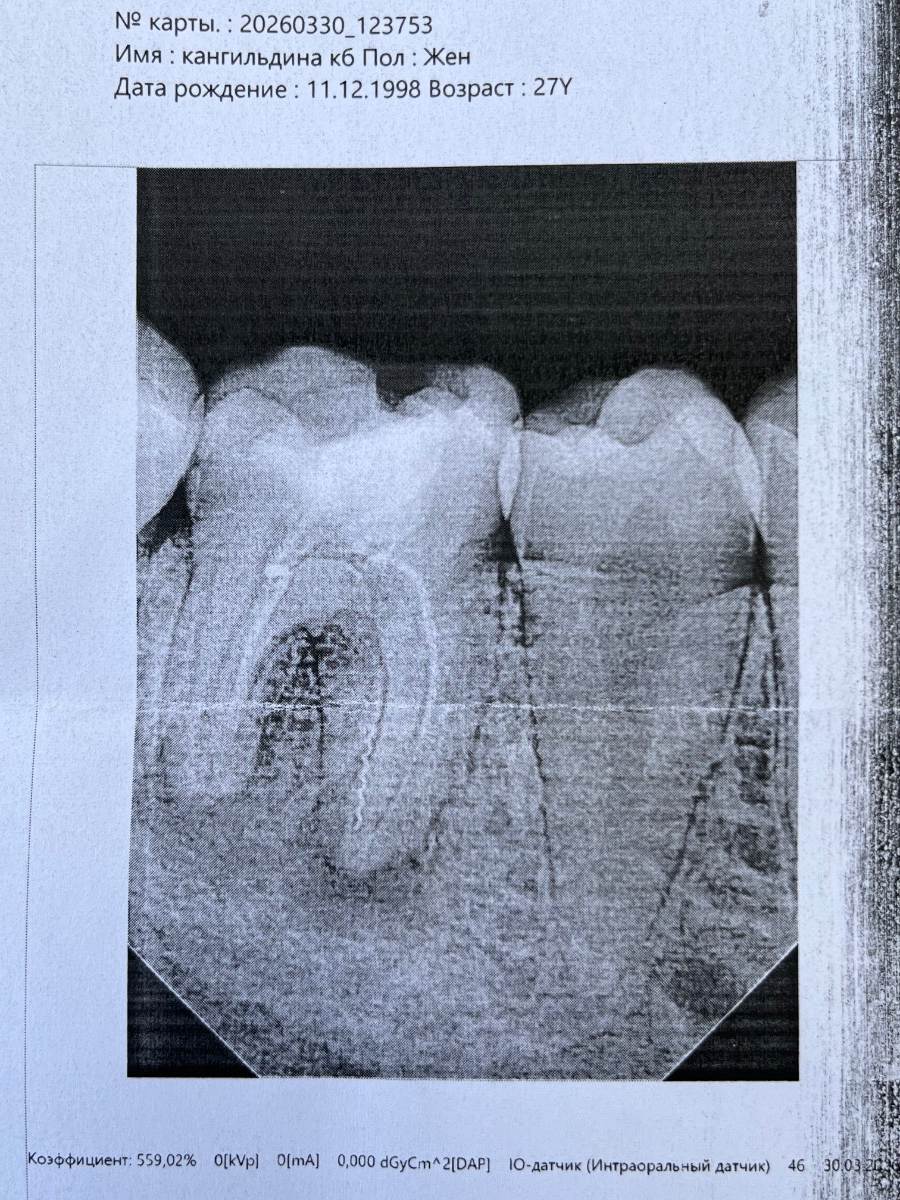

Ущзазахахахаххахахахв Опубликовано 8 часов назад Поделиться Опубликовано 8 часов назад Скажите пожалуйста, удастся ли спасти зуб при корневой инфекции? Мне этот зуб лечили лет 5-6 назад, и видимо некачественно. Сегодня была на консультации, сказали только удаление так как гной находится между 2 корнями. Но уж очень сильно хотелось бы спасти((( Ссылка на комментарий

red_butler Опубликовано 3 часа назад Поделиться Опубликовано 3 часа назад Здравствуйте, если судить только по этому снимку плохого качества, то зуб можно сохранить. почитайте эту тему Ссылка на комментарий

Гарриевич Опубликовано 4 минуты назад Поделиться Опубликовано 4 минуты назад 7 часов назад, Ущзазахахахаххахахахв сказал: Скажите пожалуйста, удастся ли спасти зуб при корневой инфекции? Мне этот зуб лечили лет 5-6 назад, и видимо некачественно. Сегодня была на консультации, сказали только удаление так как гной находится между 2 корнями. Но уж очень сильно хотелось бы спасти((( Зуб сохранить можно в переднем корне сломан фрагмент инструмента Ссылка на комментарий